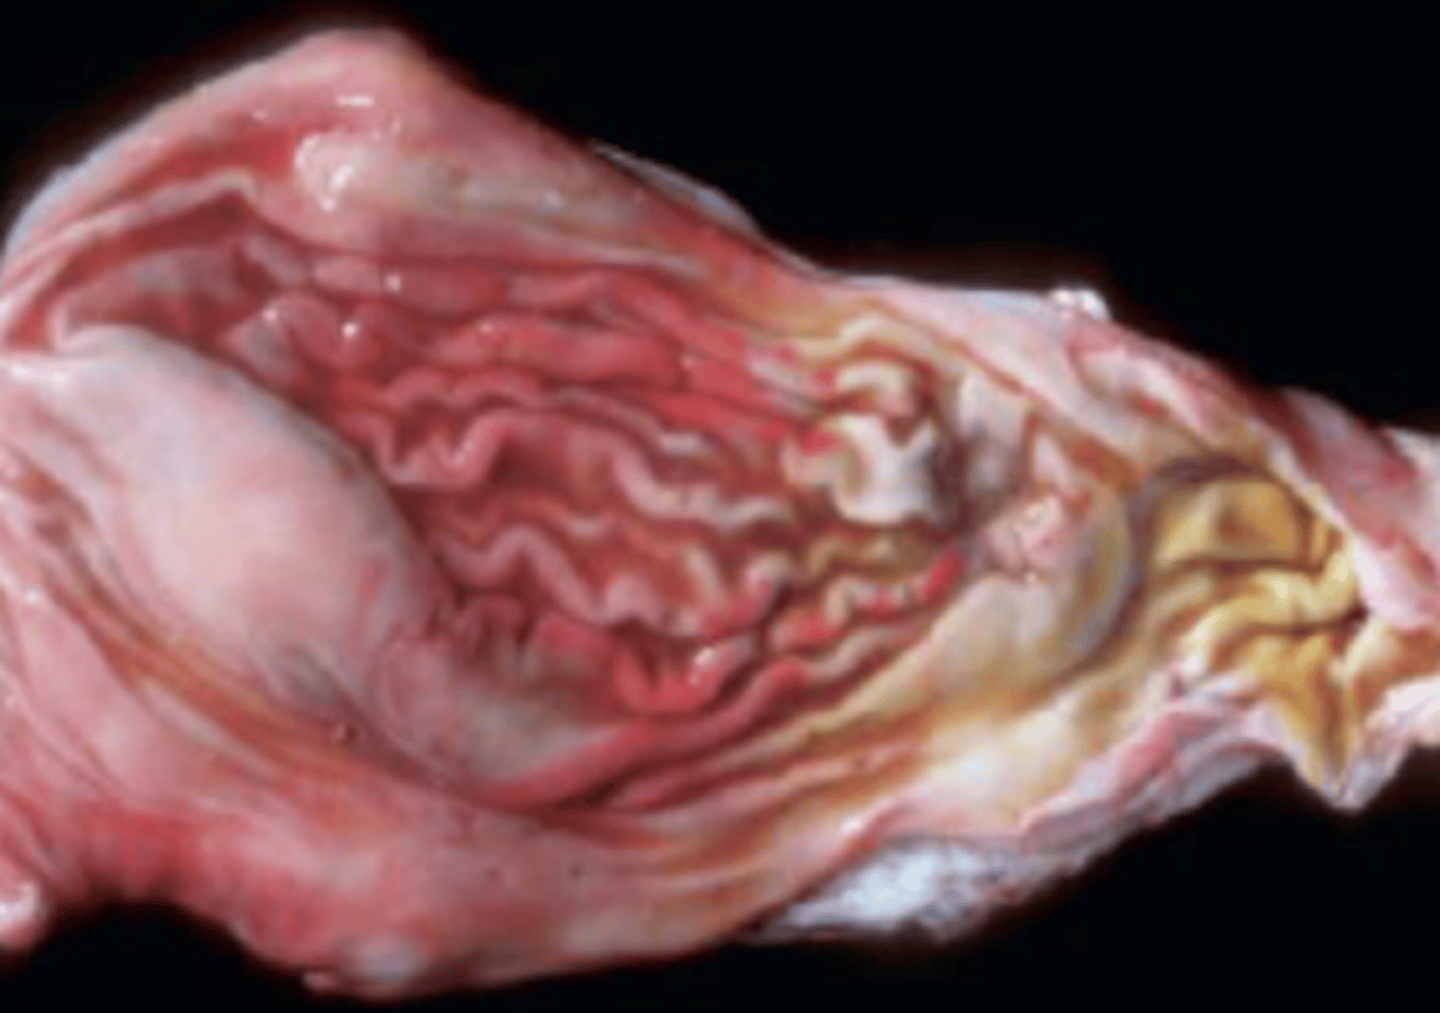

Identify the pathology?

Canine gastric dilation and volvulus (GDV)

- Large breed/ deep chested

Explain the pathology of GDV?

Fundus twists and greater curvature is displaced ventrally and duodenum will be moved dorsally and caudally

How dose GDV lead to death?

Decreaed blood flow to heart leading to pulmonary and Cardiovascular depression -> shock/ myocardial dysfunction